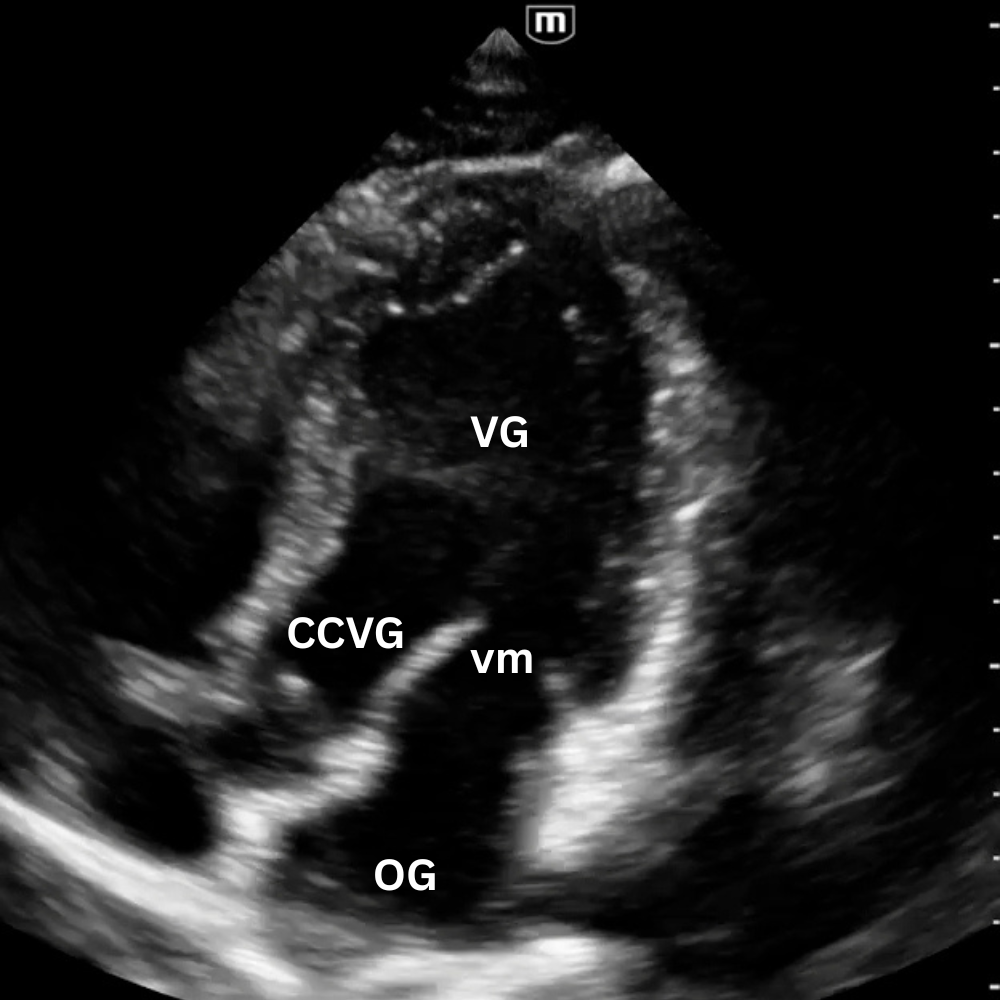

🔹 Vue Apicale Quatre Cavités

→ Quelle cavité domine ?

Placer la sonde près de l’apex (5e espace, région du mamelon gauche), marqueur vers l’épaule gauche. Glisse légèrement jusqu’à un bon espace intercostal, puis bascule la sonde vers la base du cœur jusqu’à voir VG, VD, OG et OD dans le même plan.

On visualise les quatre cavités, les valves mitrale et tricuspide et le septum.

Permet de comparer VD et VG (surcharge droite si VD ≥ VG), d’apprécier la cinétique globale et de repérer un épanchement péricardique circonférentiel.